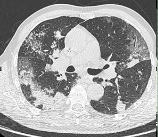

Covid-19

cas du mois

Dépistage du cancer du poumon

La Société d’Imagerie Thoracique (SIT) est une société d’organe affiliée à la Société Française de Radiologie (SFR) animée par des radiologues experts en imagerie thoracique, dans le but de promouvoir l’enseignement, la recherche (radiographie, TDM, angioscanner, IRM, appliqués aux poumons, plèvre, médiastin, cœur et vaisseaux) et les formations (Journée de Printemps, ateliers…), cas cliniques, articles, informations professionnelles et grand public visant à améliorer et diffuser les connaissances.

Les grandes thématiques sont : l’oncologie et le dépistage du cancer du poumon, les nodules pulmonaires, les pneumopathies interstitielles diffuses, les pneumopathies infectieuses, les maladies des voies aériennes et des vaisseaux pulmonaires.